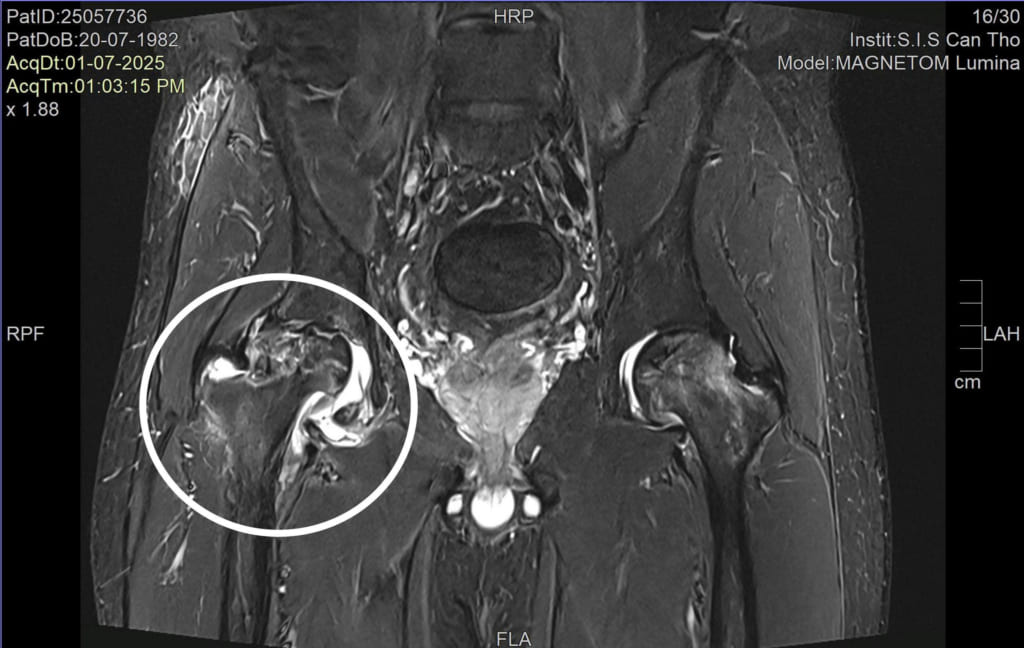

Theo ThS.BSNT.CKI Nguyễn Trần Duy – Khoa Ngoại tổng hợp Bệnh viện Đa khoa Quốc tế S.I.S Cần Thơ, kết quả thăm khám và chụp chiếu tại bệnh viện cho thấy anh V. bị hoại tử chỏm xương đùi cả hai bên, với mức độ hoại tử bên phải là độ 3 và bên trái độ 2. Đây mới là nguyên nhân thực sự gây đau nhức vùng hông và hạn chế vận động của anh V.

Chúng tôi đã quyết định phẫu thuật thay toàn bộ khớp háng cho bệnh nhân bằng vật liệu ceramic chống mài mòn cao, giúp kéo dài tuổi thọ khớp háng và cải thiện chất lượng sống” – bác sĩ Duy chia sẻ.